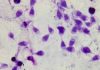

Biểu hiện mụn rộp sinh dục: Nguồn internet